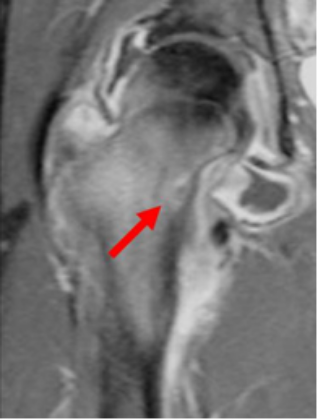

症例

右大腿骨に見られた類骨骨腫は、治療後には完全に死滅しています。治療前には強い痛みがありましたが、治療直後より完全に消失しました。このように類骨骨腫の症例では、治療後にほとんどの場合は劇的に痛みが改善します。

治療前

治療後